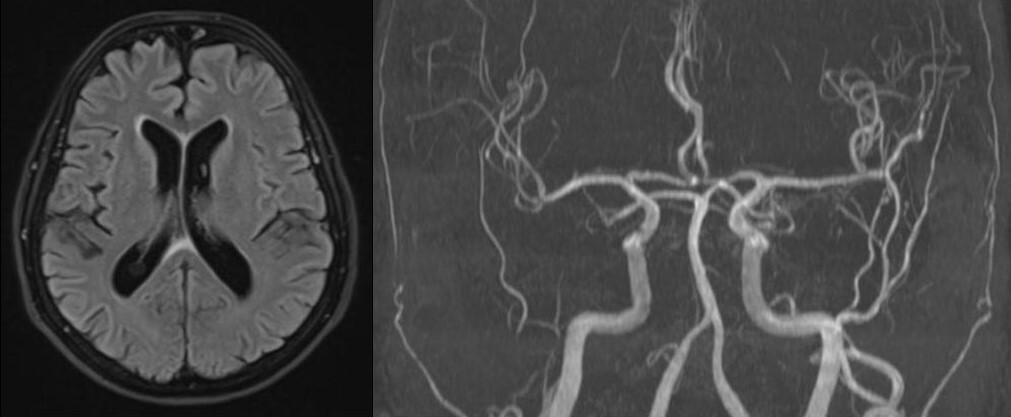

Head magnetic resonance angiography (MRA) and venography with contrast were within normal limits (Fig. 2). Erythrocyte sedimentation rate and CRP levels were normal. The halo sign on both temporal and axillary artery ultrasound was absent. The Southend Giant Cell Arteritis Probability Score (GCAPS) score was 15 [1].